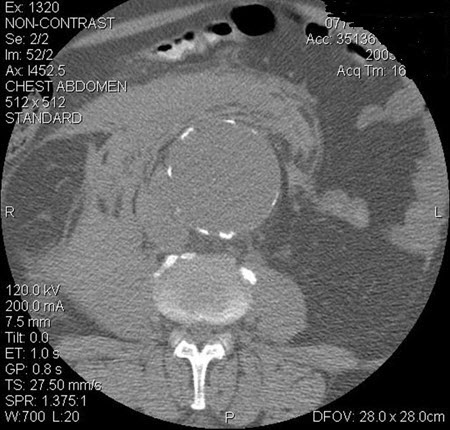

[Figure caption and citation for the preceding image starts]: Aneurisma da aorta abdominal: tomografia computadorizada (TC) de um aneurisma da aorta abdominal rotoUniversity of Michigan, mais especificamente os casos do Dr. Upchurch, representando os Departamentos de Cirurgia vascular e Radiologia [Citation ends].